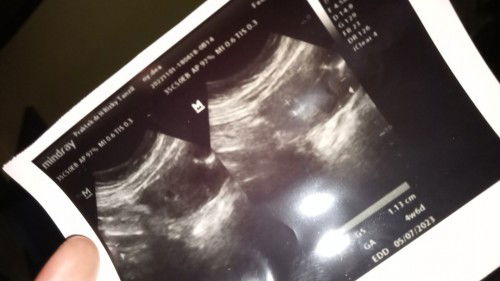

Vitamin dari bidan dan vitamin waktu usg

Bun mau nanya dong..kan waktu tau positif sya langsung cek ke bidan ,nah kan di ks vitamin buat 1bulan,nah tgl 1 kemarin sya usg beda tmpt karena di bidan yg awal sya periksa gda usg, dan di ks vitamin jga hanya untuk 10hr..gimana ya bun apa abisin dlu vit dari bidan apa bisa selangseling🙏mhon tanggapan ny bunda2..semoga sehat selaluu🤲🥰#ingintahu